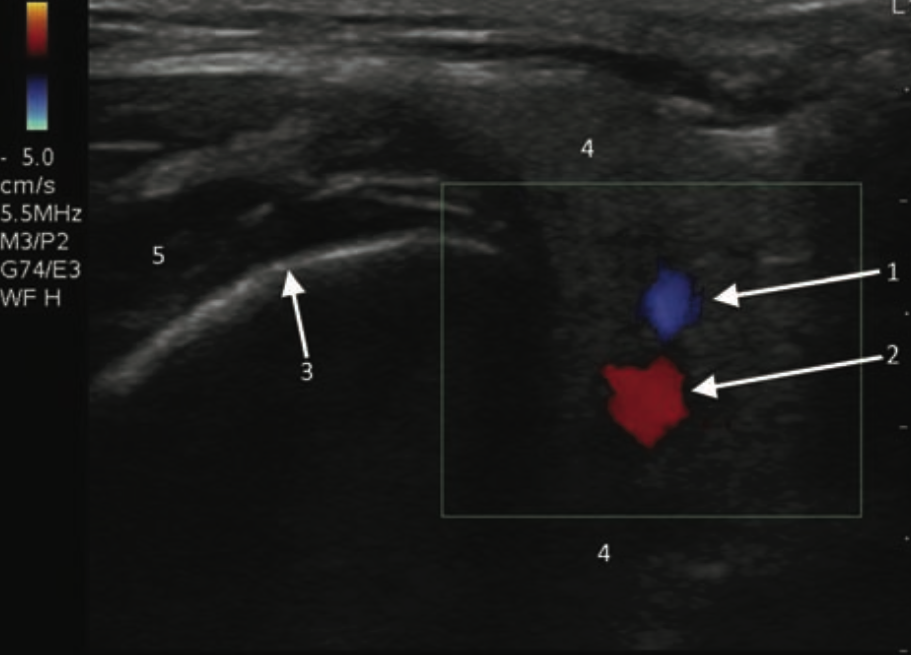

- Superficial and deep lobes divided by plane in which the facial nerve is located, which is superficial to the retromandibular vein and lateral to the external carotid artery.

- Figure 14. Parotid gland (https://commons.wikimedia.org/w/index.php?curid=4024415)

- The difficult to visualize facial nerve and deep lobe of the parotid obscured by the mandible, can be compensated by visualization of the retromandibular vein as a sonographic landmark separating the superficial and deep lobes of the parotid gland.

- The superficial lobe overlies the masseter muscle, extending posterior to the angle of the mandible.

- Intraparotid lymph nodes are frequently found in the parenchyma of the upper and lower poles.

- Figure 15 and 16. Transverse view of normal left parotid gland with color doppler on vessels (1- Retromandibular vein; 2- External carotid artery; 3- Surface of the mandible; 4- Parotid gland; 5- Masseter muscle)